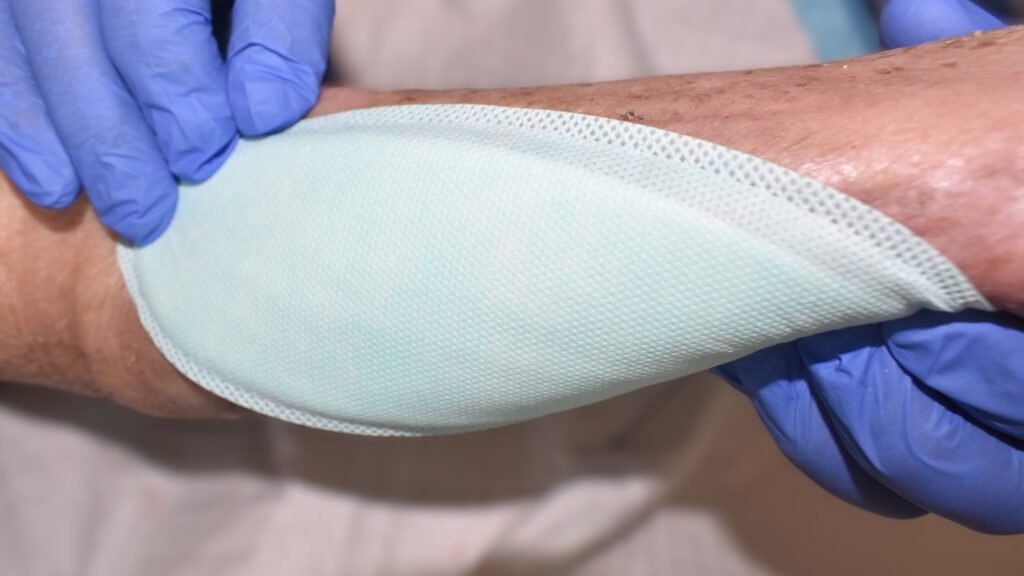

kliniderm alginate standard und kliniderm alginate cavity bestehen aus Kalzium-Alginat-Fasern, die sich durch Ionenaustausch in ein hydrophiles, sehr saugfähiges Gel umwandeln. Die Cavity-Variante lässt sich gut als Wundfüller in tiefen und unterminierten Wunden einsetzen.